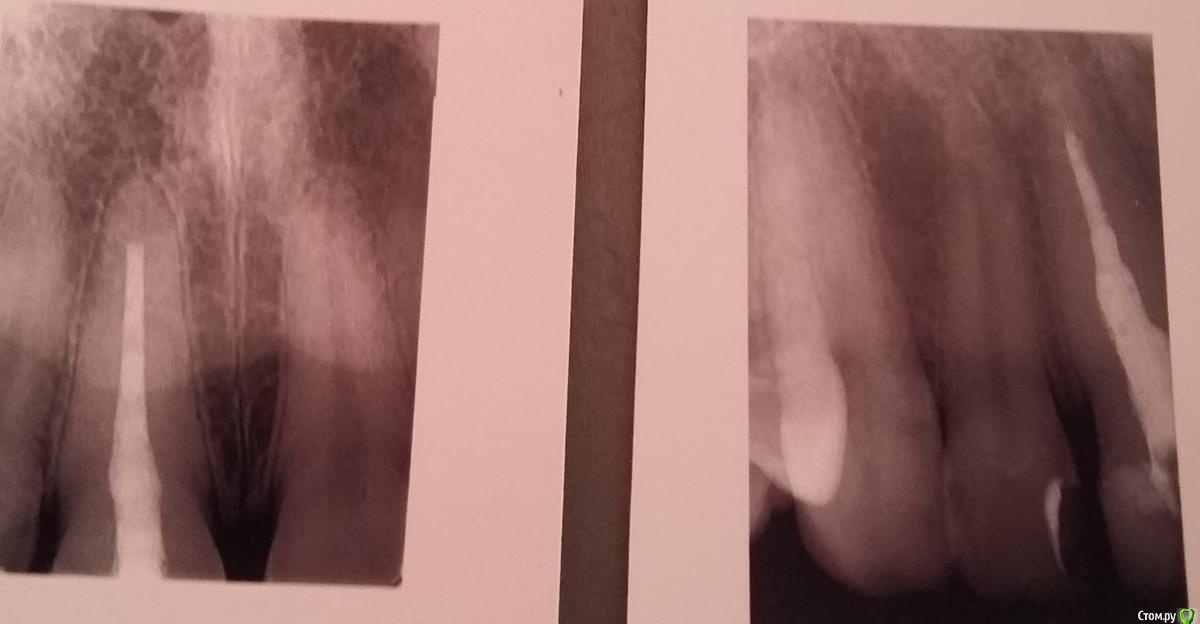

Ирина. Опубликовано 17 августа, 2015 Автор Поделиться Опубликовано 17 августа, 2015 (изменено) На этом снимке изображение слева - до перепломбировки канала, справа - после перепломбировки Изменено 17 августа, 2015 пользователем Ирина. Ссылка на комментарий

Ирина. Опубликовано 18 августа, 2015 Автор Поделиться Опубликовано 18 августа, 2015 Коффердам не использовали точно. Перелечивали в 2 этапа. 1 день распломбировка.Второй - перепломбировка. Перепломбировка длилась около получаса. В процессе и по завершению много раз делались снимки (раза 4-5).Чем запломбировали канал, к сожалению, не знаю. Но клиника престижная, не думаю, что чем-то устаревшим. Дело в том, что в клинике со 100% уверенностью утверждают,что канал пройден до конца,гарантированно заверяют,что никогда не будет ни кисты, ни гранулемы, пустоты нет. Показывают мне какую-то тоненькую ниточку пломбировочного материала в апикальной части.Но почему-то ее вообще не видят другие врачи.Я уже и не знаю, кому верить. Ссылка на комментарий

Ирина. Опубликовано 18 августа, 2015 Автор Поделиться Опубликовано 18 августа, 2015 Сегодня пломбировали соседнюю двойку. Вот там даже я вижу своим непрофессиональным взглядом,что канал пройден до конца. В единице не вижу Ссылка на комментарий